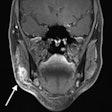

Can MRI help detect early periodontitis?